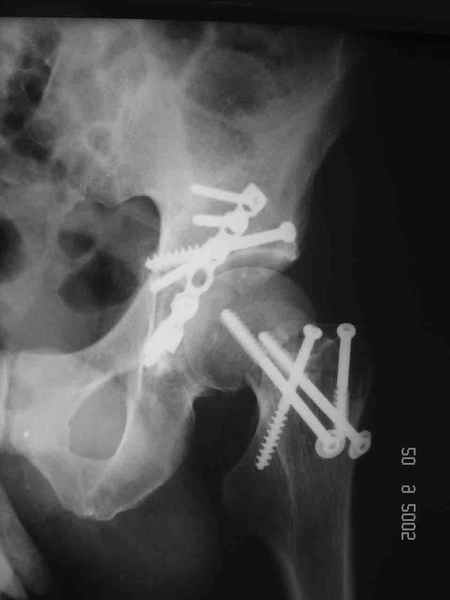

Привет! Вот недавно прооперировали похожий на ваш случай - впадина + шейка (правда у нас впадина поперечный+задний край). После травмы прошло 4 недели. мужчине 46 лет. С такой комбинацией все показания к первичному протезированию. Морально и технически мы к этому уже созрели.Но больной не собрал денег на протез. Выполнили остеосинтез впадины и шейки, прекрасно понимая, что головка вскоре рассосется, мы хотя бы надемся что к этому времени таз срастется, как говорится создали все условия для дальнейшего протезирования (может, и протез в последующем подешевле будет, в смысле, без укрепляющего кольца?). Привет Рункову!

Привет Алекей! Сделано неплохо, поздравляю, хотя второй винтик можно было бы и подлиннее в шейку загнать! Пара вопроов: доступ такой же? головка была свободной или висела на капсуле?

Согласен, можно было и подлиннее. Доступ такой же - чрезвертельный, только разрез кожи прямой (а не Y, чего то я разницы не ощущаю). Головка была абсолютно свободной (то есть во время остеосинтеза таза лежала в стакане и не мешалась). Шансов, что она прирастет 0,00001%. Хотели даже выбросить, но привинтили как временный биологический протез (читай свободный трансплантат), чтоб на период срастания таза бедро проксимально не ушло (может ортопеды потом спасибо скажут). Ну а у вас первичное протезирование при переломе впадины тоже пока полько в планах?